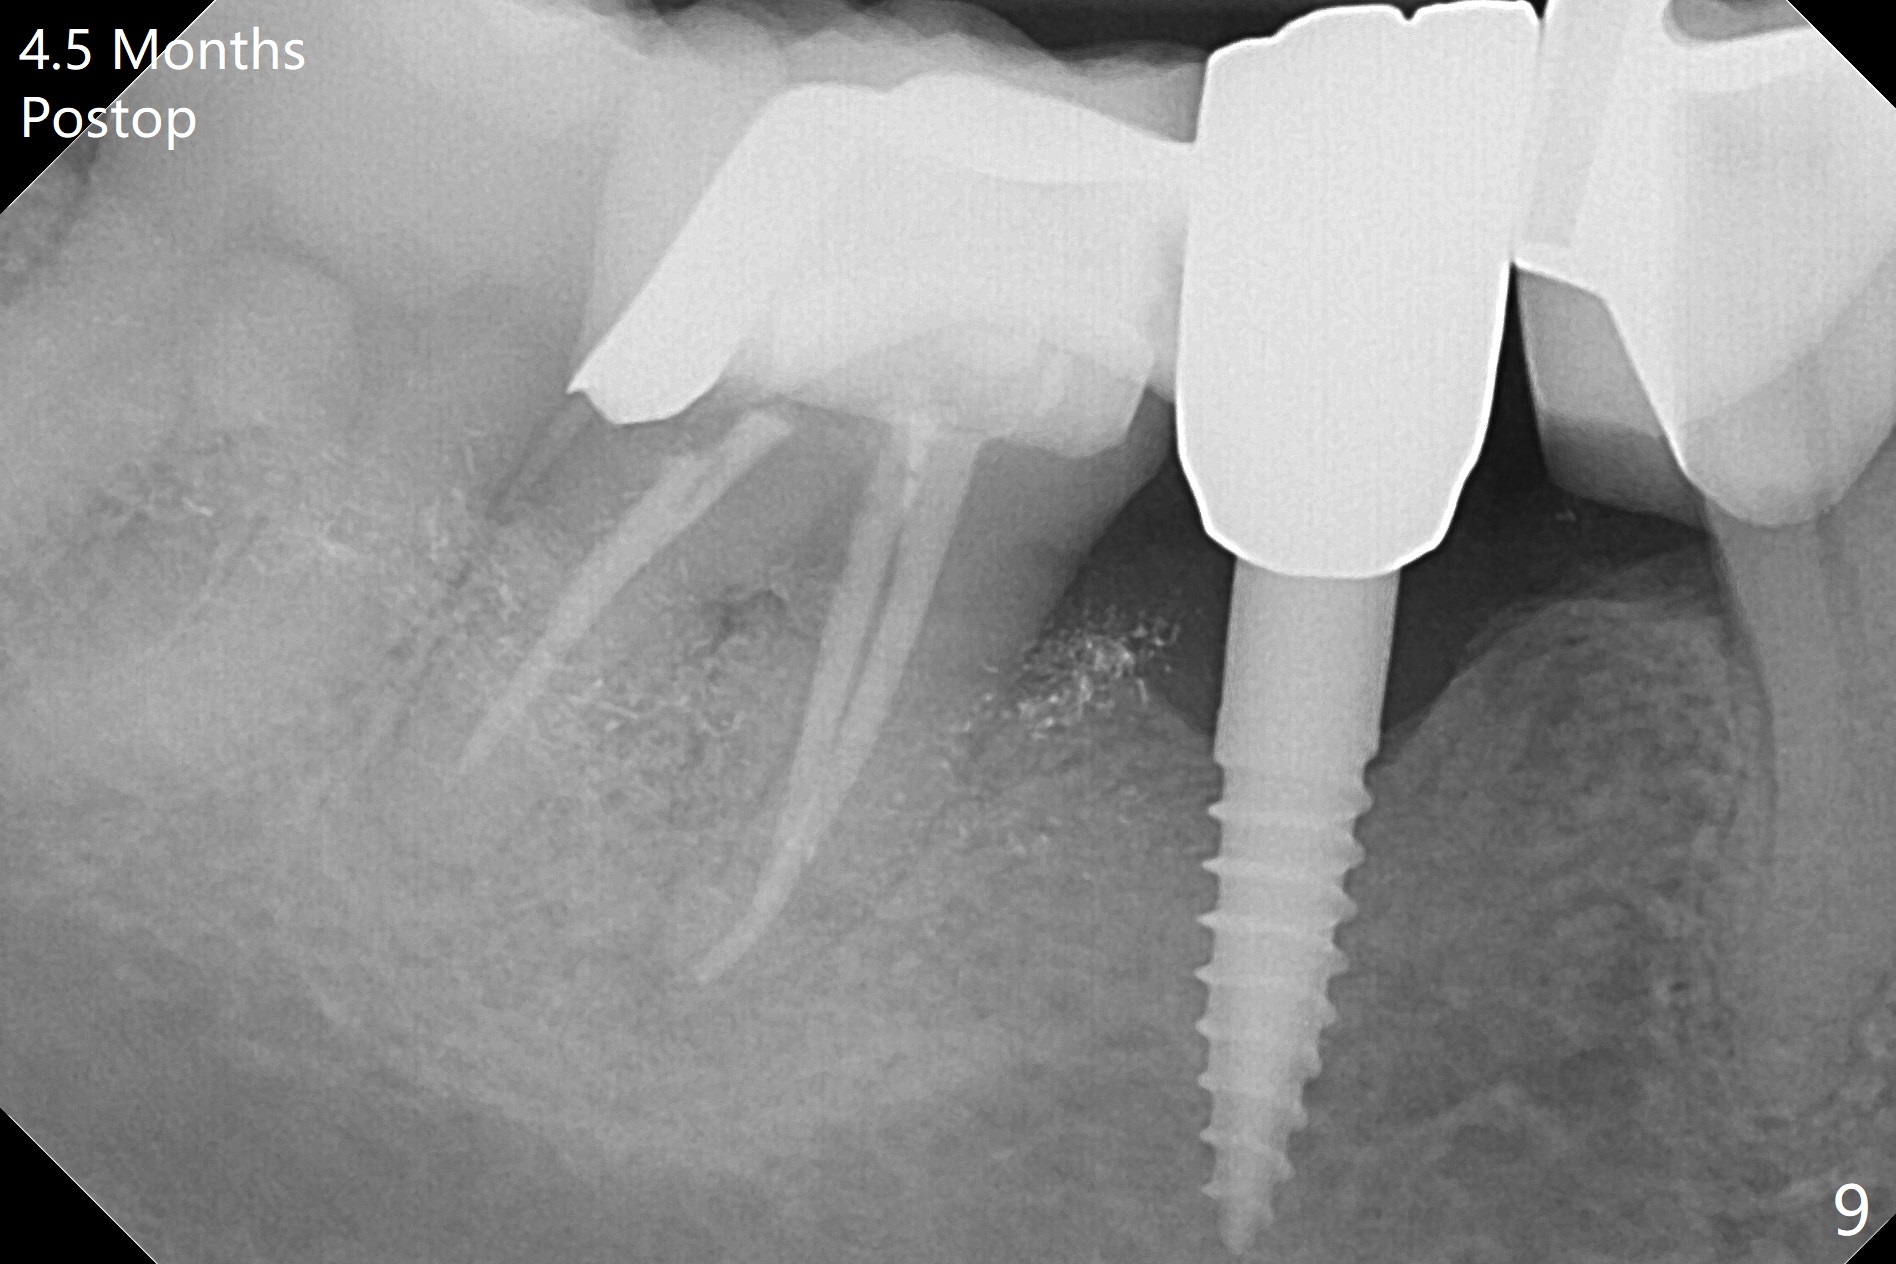

There is a space underneath the pontic at #30 (Fig.1 *), the basis for food impaction. After sectioning between the pontic and the posterior retainer, the pontic is removed from the anterior retainer with an attachment (Fig.2 *). The initial depth of osteotomy is 10 mm following ridge top reduction (Fig.3). A 3x10(4) mm 1-piece implant is placed with >50 Ncm; to reduce possibility of crown dislodgement from the implant, the retainers will be kept with modification of the proximal surfaces as shown by curved lines in Fig.4. Periodontal dressing is applied after suturing. There is no postop paresthesia. The periodontal dressing remains in place 2 weeks postop because of engagement into the attachment slot and undercuts (Fig.5). The patient returns 3 months postop; after minor contour adjustment (Fig.6 red curved line), impression is taken. The permanent crown is temporarily cemented (3.5 months postop) in case of food impaction due to the distal overhang of the tooth #29 (Fig.7). In fact the patient returns 4.5 months post cementation with right TMD (muscle relaxant prescribed) and food impaction, although there is no bone resorption (Fig.8,9). It appears that the crown at #29 needs to be redone, while porcelain will be added to the mesial surface of the one at #30 (Fig.10 red lines). In fact the crown at #30 is redone because of loose proximal contact with #31; there is no bone resorption 13 months post cementation (Fig.11). Bone resorption remains unnoticeable 28 months post cementation (Fig.12,13).